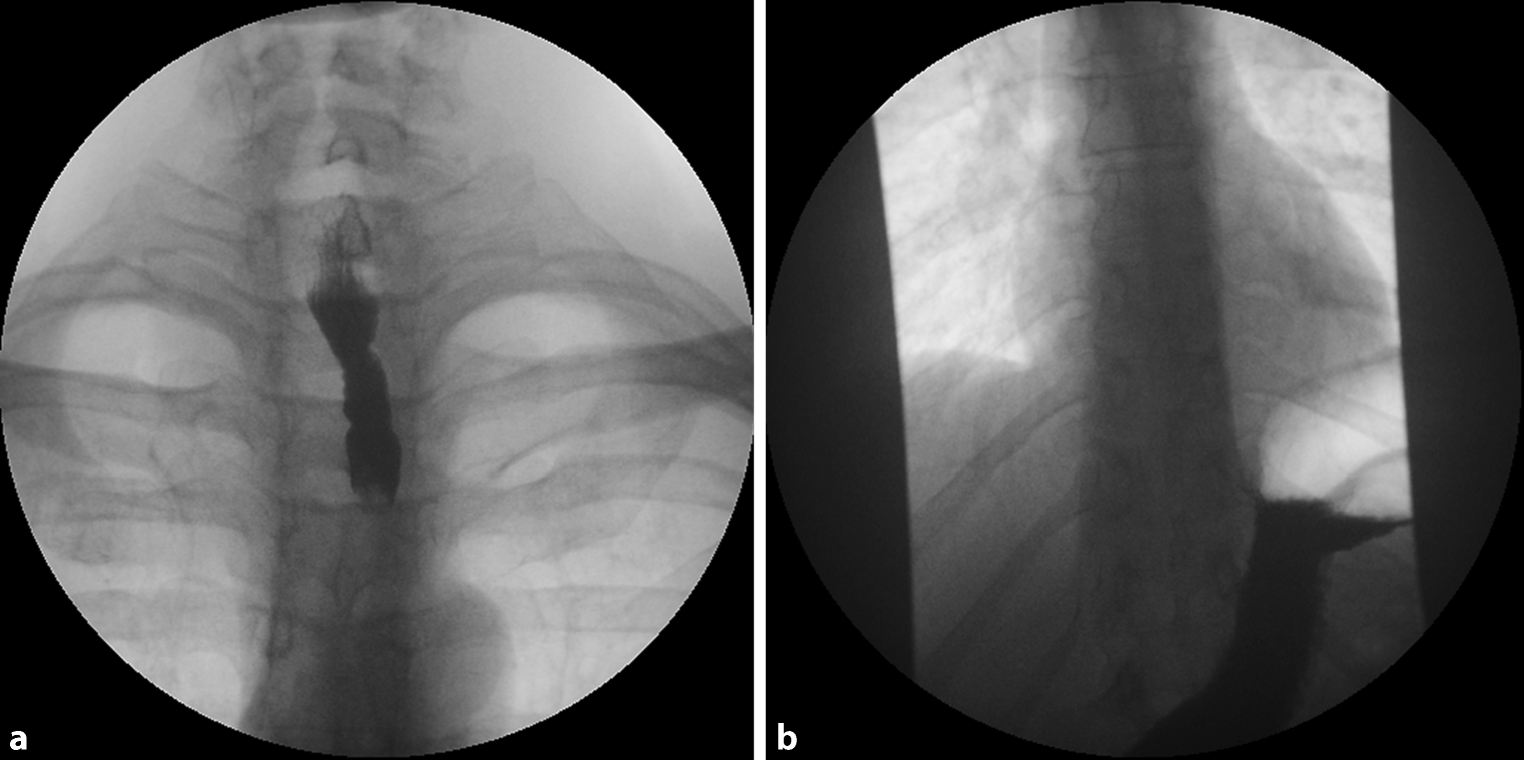

Manometry revealed a slightly prolonged duration of swallowing with minimal nonspecific alterations, probably due to mild esophageal spasm. On endoscopy, multiple areas of the esophagus appeared like crepe paper with thickened mucosa, there were white plaques, longitudinal furrows and minimal circular rings (Fig. 2). Biopsies were taken from multiple sites in the distal 10 cm of esophagus.

Fig. 2

Esophagoscopy shows white plaques (arrows) and a laceration (L) with sloughed-off mucosa and some bleeding. Discrete circular rings (R) are also visible